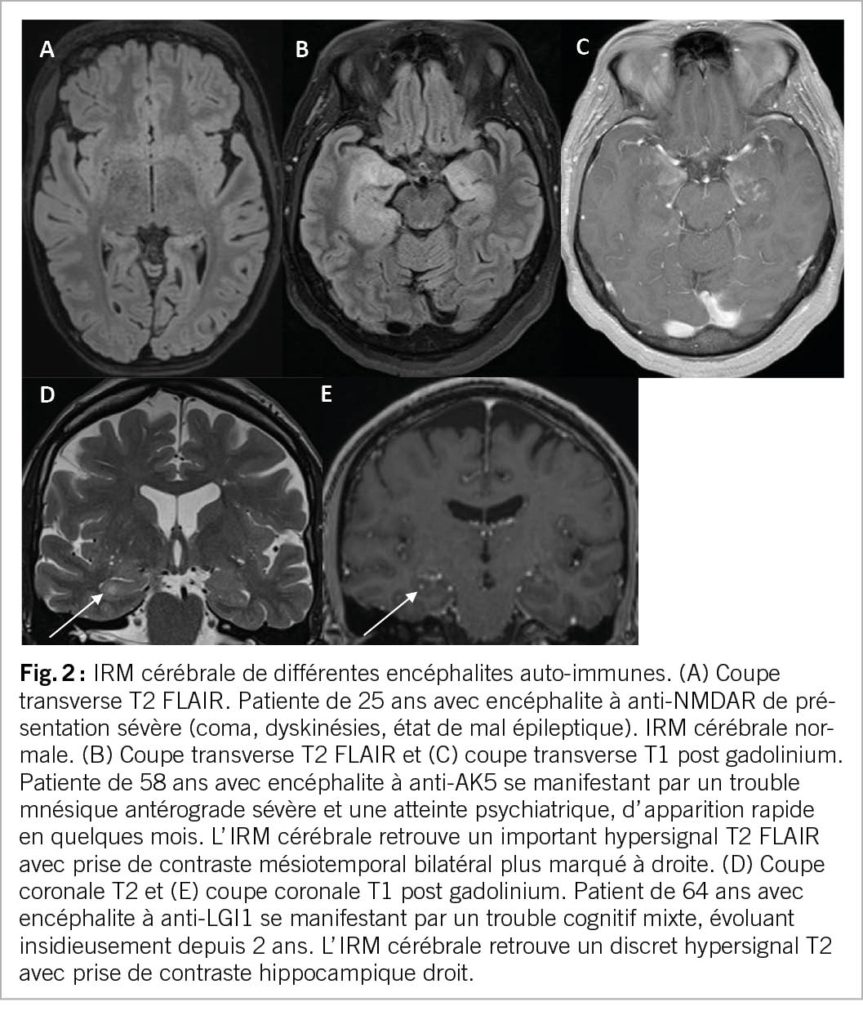

L’ atteinte radiologique est variable selon l’ anticorps incriminé, avec une IRM qui peut être normale, comme dans la moitié des cas d’ anti-NMDAR (Fig. 1A) (4). En cas d’ encéphalite limbique comme celle à anti-LGI1, l’ IRM cérébrale peut trouver un hypersignal T2 FLAIR de la région mésiotemporale uni- ou bilatéral, parfois associées à une tuméfaction et prise de contraste hippocampique (Fig. 1B-E) (5). Ce tableau radiologique n’est cependant pas spécifique, et peut se voir dans des encéphalites infectieuses (HSV-1), des gliomes ou des états de mal épileptiques. D’ autres images ont été décrites, comme des atteintes multifocales, une atteinte des ganglions de la base ou une atteinte diencéphalique. L’ IRM permettra également d’ exclure des diagnostics alternatifs, comme une atteinte infectieuse, tumorale ou une maladie à prion.